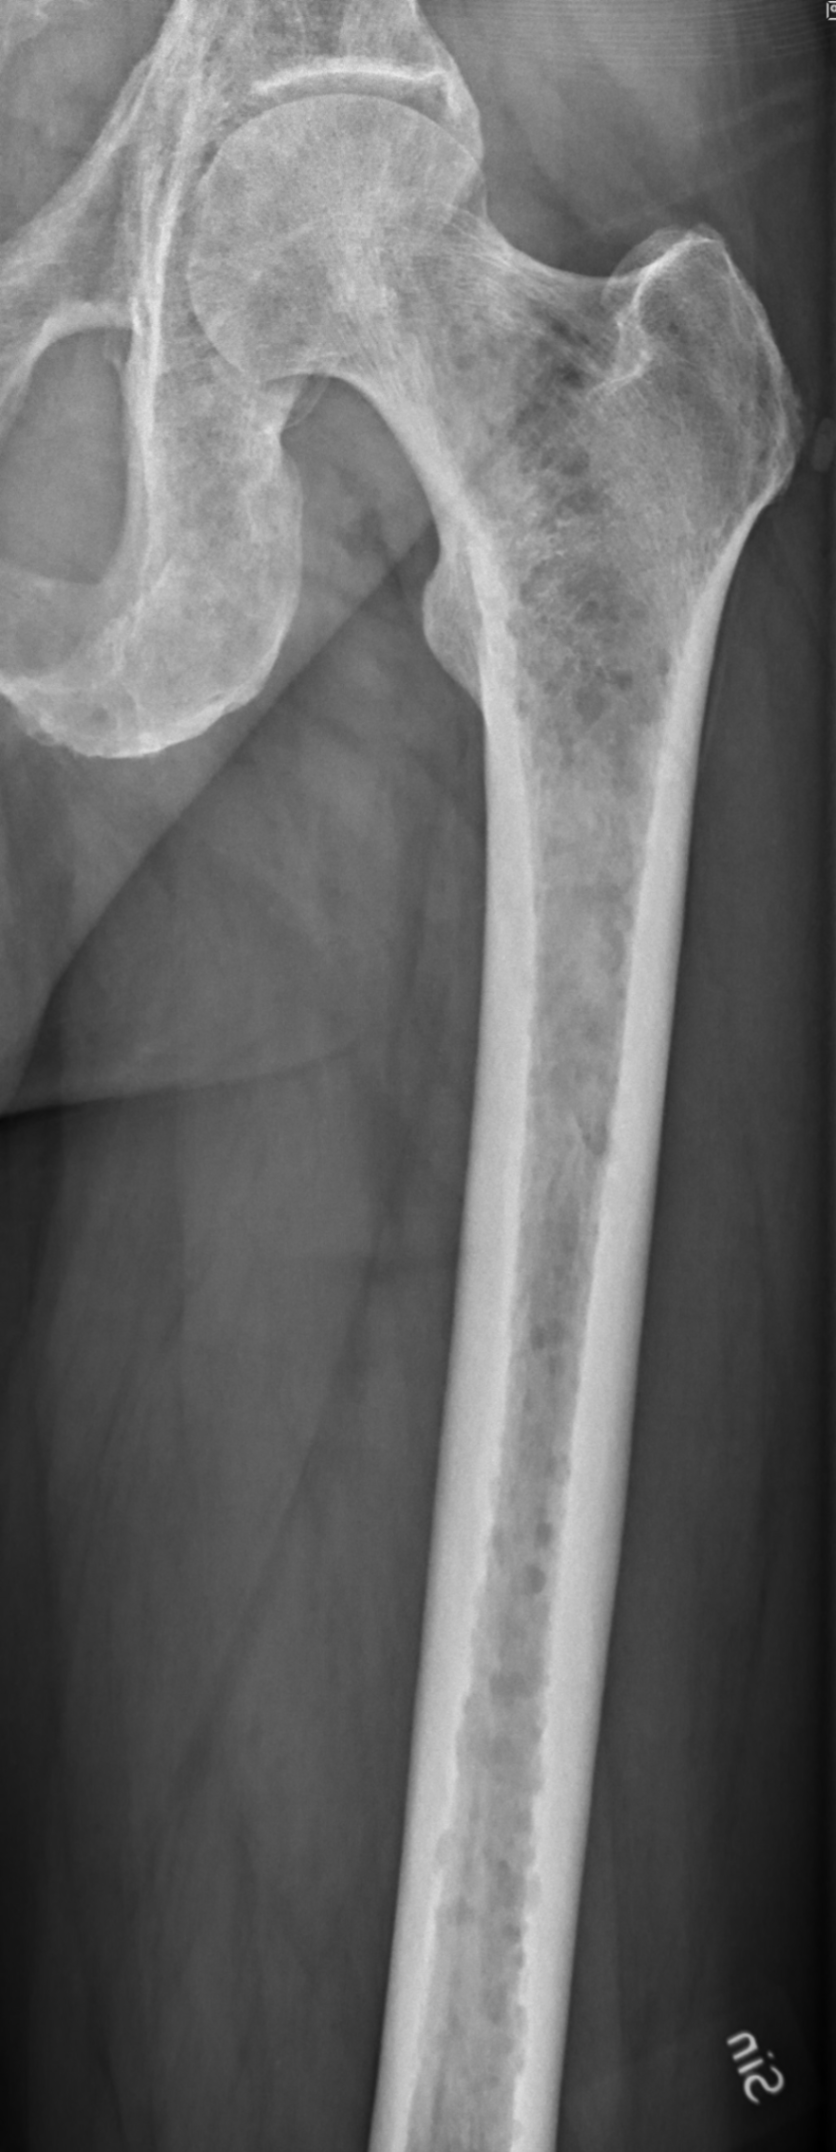

축골격(axial skeleton)의 파괴성 형질세포종(plasmacytoma): 척추, 늑골, 두개골, 골반, 대퇴골, 쇄골, 견갑골 등이 흔히 침범

골수강에서 시작해 피질골을 침식하며 “punch-out 병변”(1–4cm 크기)의 방사선 소견을 보임 Left femur with myeloma, Wikimedia Commons